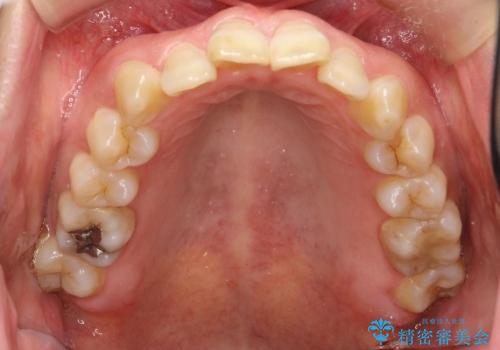

- 上下の歯並びにガタつきがあり、また、上下前歯の前後のズレが大きく上の前歯が突出しています。

インビザラインではガタつき(叢生)の改善だけでなく、上下の前後的なズレについてもアプローチが可能です。

インビザラインの特色を生かした歯牙移動計画を作成し、非抜歯にて治療を行いました。

マウスピース枚数 初回52枚 + 追加19枚 + 追加12枚

上の歯列に後方への力をかけるために、患者様には顎間ゴムをマウスピースと共に併用してもらいました。

当院独自の工夫を随所に盛り込み、狙い通りの治療結果が得られました。